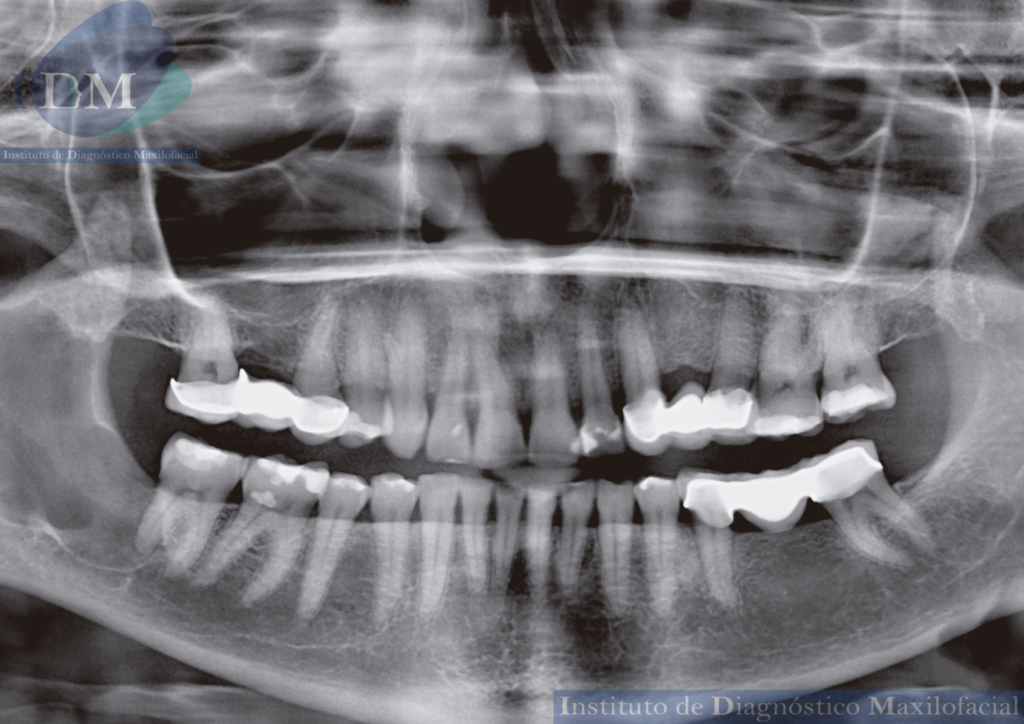

Radiografia Panorámica

A la evaluación de la radiografía panorámica se observa una imagen radiopaca corticalizada y de borde definidos en cuerpo y rama mandibular del lado derecho.